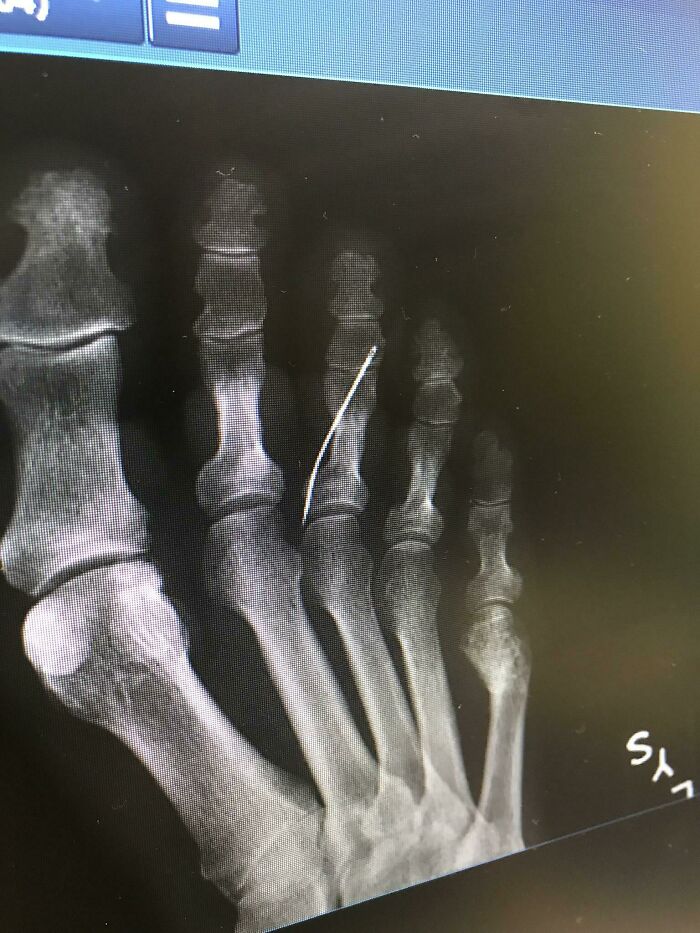

My Grandma Had No Idea She Had A Sewing Needle In Her Foot. No Telling How Long It’s Been In There. Skin Was Healed. It Finally Started Rejecting Yesterday And She Had Emergency Surgery